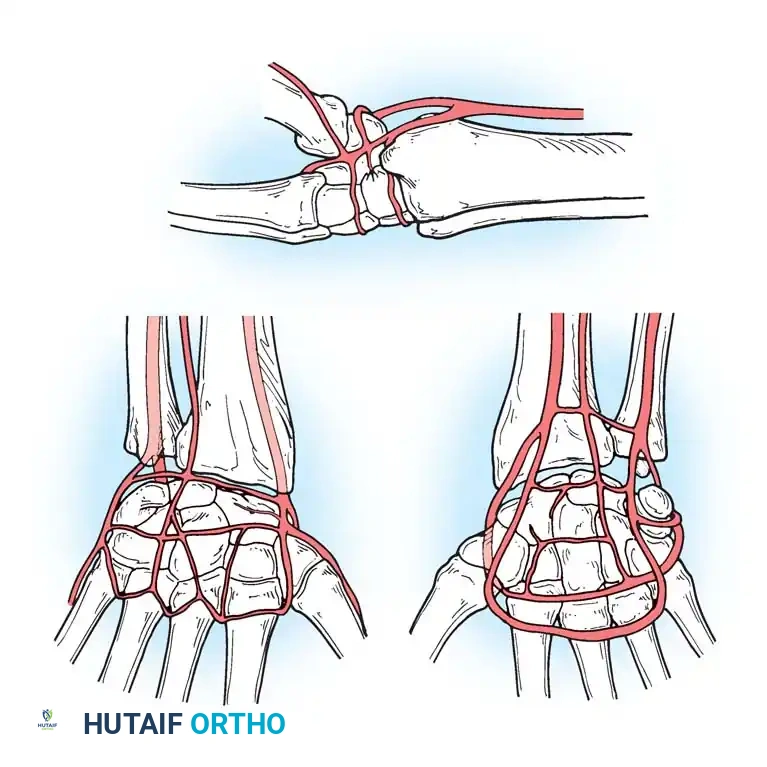

Vascular Anatomy of the Carpus

Understanding the extraosseous and intraosseous vascularity of the wrist is paramount, particularly when managing fractures of the scaphoid and lunate, which are highly susceptible to avascular necrosis (AVN).

Gelberman et al. mapped the terminal branches of the radial, ulnar, and anterior interosseous arteries, which form three dorsal and three palmar transverse arterial arches.

Dorsal Arterial Arches

- Dorsal Radiocarpal Arch: Supplies the proximal lunate and triquetrum.

- Dorsal Intercarpal Arch: The largest arch, supplying the distal carpal row and providing anastomotic flow to the lunate and triquetrum.

- Basal Metacarpal Arch: Supplies the distal carpal row and metacarpal bases.

Palmar Arterial Arches

- Palmar Radiocarpal Arch: Supplies the palmar lunate and triquetrum.

- Palmar Intercarpal Arch: Highly variable; rarely contributes nutrient vessels to the carpus.

- Deep Palmar Arch: Consistent arch communicating with the dorsal basal metacarpal arch.

Surgical Warning: The scaphoid receives 70-80% of its blood supply from branches of the radial artery entering the dorsal ridge, perfusing the bone in a retrograde fashion. Fractures at the scaphoid waist or proximal pole disrupt this delicate supply, leading to high rates of nonunion and AVN. Surgical approaches must meticulously preserve the dorsal ridge vasculature.